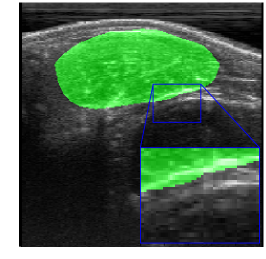

Rib Eye Area (REA). This image dataset consists of ultrasound images of the Longissimus dorsi muscle between the 11th and 13th ribs of cattle. The goal is to automatically calculate the rib eye area (REA), an important region for decision making during cattle breeding. The main challenge is the uncertainty in the REA annotation, since the image is noisy and even experts have difficulty in delimiting the borders of this region. Fig. 3 presents examples of images and the annotation made by a specialist. We can observe that some borders are absent and depend on the subjectivity and knowledge of the annotator. To evaluate the segmentation methods, 76 images with resolution were obtained and labeled by an expert. Due to the number of images, the division of the images in training and testing followed 5-fold cross-validation.

REA dataset. This image dataset has high uncertainty during labeling due to noise from the ultrasound image. In some cases, the border of REA is not completely visible and must be estimated by the specialist. Therefore, the proposed approach becomes essential to obtain accurate segmentation at the edges. The segmentation examples in Fig. 6 show that the baseline was not able to define the REA correctly due to the uncertainty of the labeling. On the other hand, the proposed approach presents results close to the specialist in regions that the border needs to be estimated.